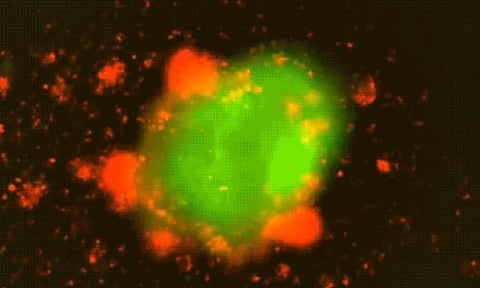

The new CAR T-cells were analysed, in lab-based experiments in mouse models, on a selection of tumour cells including prostate cancer and glioblastoma.

“We can clearly see that the ultrasound controllable CAR plus two rounds of ultrasound stimulation outperformed the standard CAR T-cells,” Liu said. “Also, when we kept challenging our CAR T-cells with tumour cells, the standard CAR was already exhausted and in a dysfunctional state, but our ultrasound controllable CAR has a better function, less exhaustion, and more enhanced killing.”